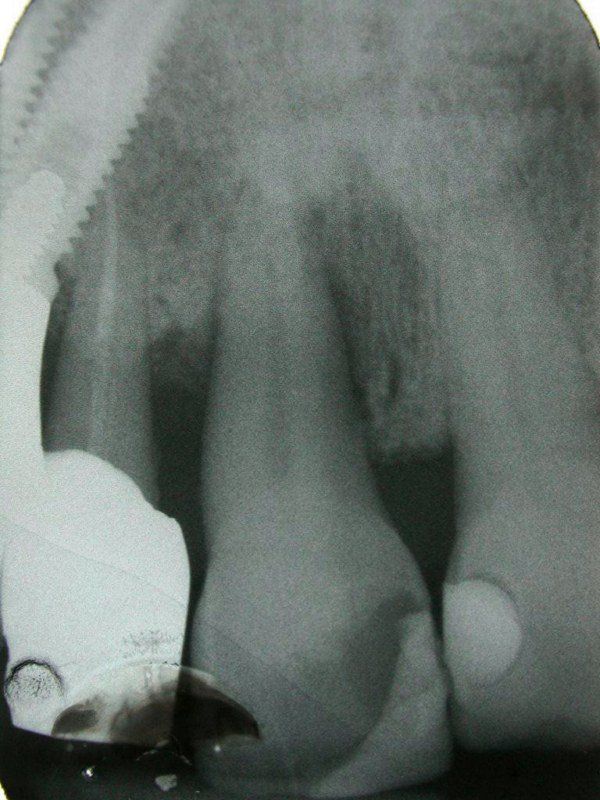

3° Caso: retrazioni gengivali